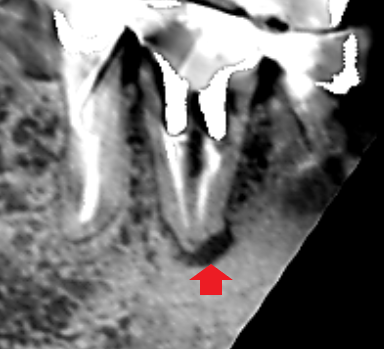

初診時の下顎第一大臼歯の冠状断のCT画像です。

矢印の先に、舌側に根の沿って長い影が認められます。歯根に沿った長い影がみられるときは、歯根破折の可能性があります。

精密根管治療6カ月後の経過観察時の冠状断のCT画像です。下顎第一大臼歯の根の舌側に拡がっていた長い膿の影が消え、歯槽骨が再生しています。膿の原因は、単なる根管治療不足でした。